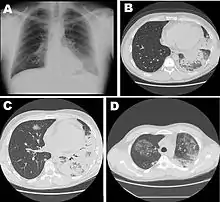

- La maladie du légionnaire, qui est une forme grave d’infection respiratoire. La maladie a été pour la première fois décrite et nommée en 1976, à la suite de la contamination de 181 personnes à Philadelphie au cours d’une convention de la légion américaine (en)[2]. La mortalité dépend de la gravité de la maladie et de la rapidité de la prise en charge. En France, l’institut de veille sanitaire rapporte que 10 à 20 % des cas sont contractés dans les hôpitaux. Pour les cas nécessitant une hospitalisation (99 %), un taux de mortalité de 15 à 20 % est observé. Aux États-Unis, le taux de mortalité, parmi les cas d’infection nosocomiale, atteint 40 %[3]. La maladie du légionnaire ne peut pas être radiologiquement ou cliniquement différenciée des autres pneumonies et requiert une analyse microbiologique pour permettre d’établir le diagnostic avec certitude[4].